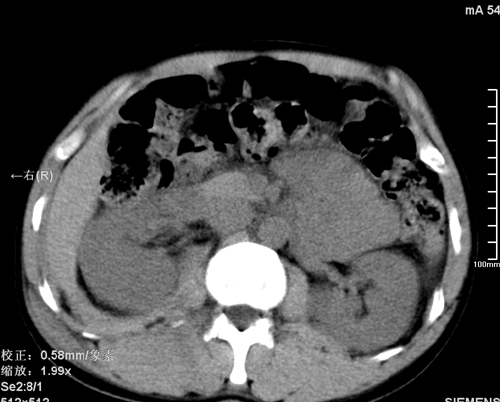

以下是引用qiushi在2008-3-28 12:00:00的发言:[br]腹膜后血肿,所见腰椎横突骨折.[br]建议上传骨窗、腰椎扫描.

以下是引用tao772在2008-3-28 12:29:00的发言:[br]右侧腹膜后积血,右侧腰大肌挫伤,右侧部分横突骨折. 肾脏最好报一下挫伤,必要时增强。